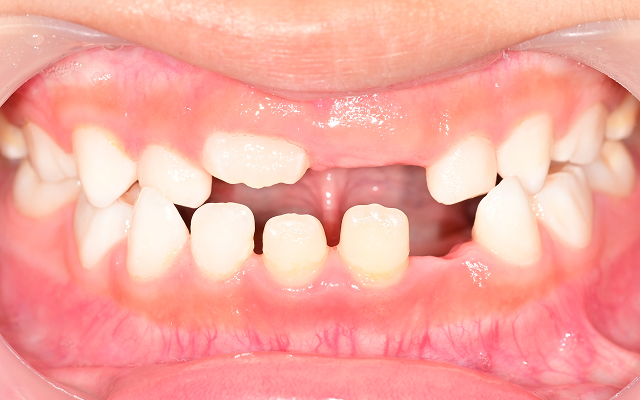

영구치가 덧니로 나거나 발치가 필요한 경우로 악화(발치교정)

• A

일반적으로 만 7세 전후, 영구치가 앞니와 어금니 일부 맹출할 때부터 가능하고, 빠르면 만5~6세 정도 유치열기 부터 가능합니다. 이 시기에 교정과 전문의의 검진을 받아, 성장 방향을 미리 점검하는 것이 중요합니다.